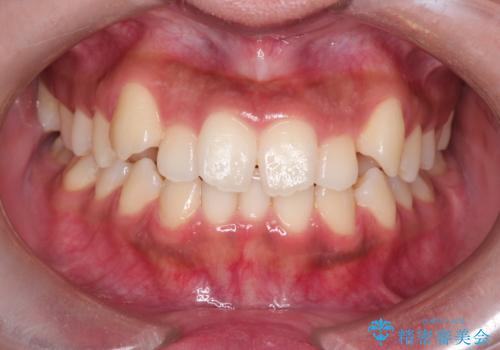

【インビザライン】笑ったときに目立つ八重歯をなおしたい

- 笑ったときに八重歯が見えることを主訴に来院されました。

下の前歯が一本足りない患者様でしたので、シミュレーションを作り、事前に患者様と治療ゴールのイメージをしっかり共有したうえでインビザラインを用いて治療を行っています。

奥歯を後ろのほうに動かすことで、前歯も少し下がることができ、矯正後の口元も満足していただきました。